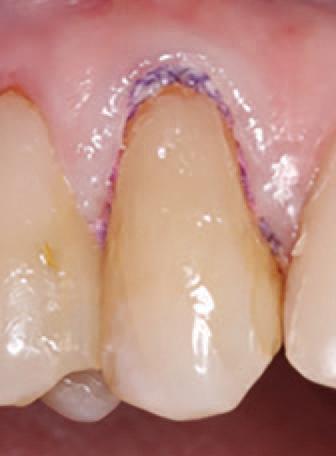

To improve isolation and soft tissue access, a retraction cord was placed before initiating the procedure (Fig. 2). The tooth was evaluated using a caries indicator dye (Kuraray Noritake Dental), helping to identify any remaining infected tissue beneath the dislodged composite (Fig. 3). Decay removal was completed with a diamond bur, and the enamel was bevelled using a starburst pattern to enhance aesthetic blending (Fig. 4). This preparation design was chosen for visual integration rather than bond strength enhancement.

Etching and Bonding